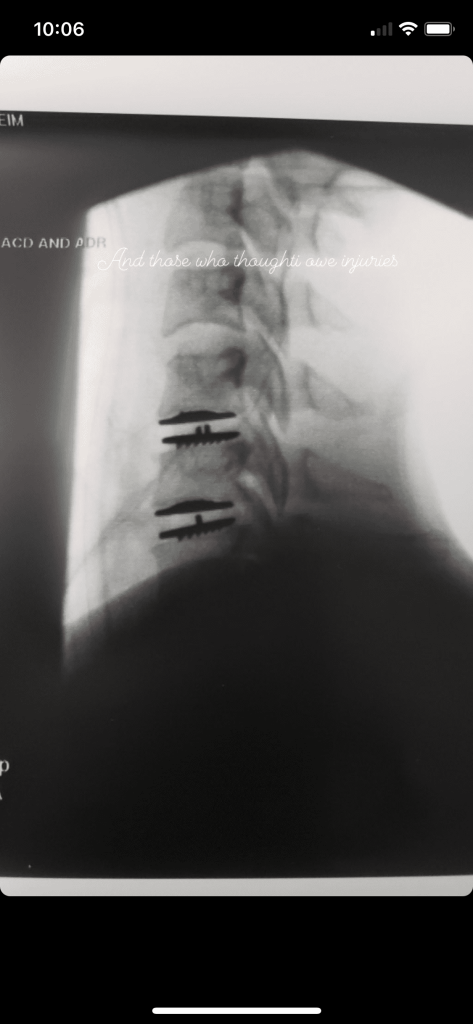

Rose then shared a a handful of videos from doctors’ visits regarding injuries she faced on set, writing, “To everyone who said I was too stiff on Batwoman, imagine going back to work 10 days after this . . . 10 DAYS! (Or the whole crew and cast would be fired and I’d let everyone down because Peter Roth said he would recast and I just lost the studio millions (by getting injured on his set) . . . Instead of spending half a day to rewrite me out for a few weeks to heal.”